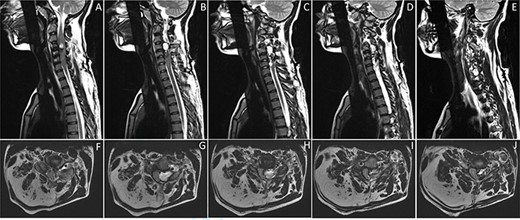

Whole spine MRI showed a C3–C6 left extradural lesion causing marked compression on the spinal cord (Fig. 1). Cerebral angiography confirmed an arteriovenous fistula (Fig. 2).

Sagittal (A-E) and axial (F-J) images of T2-weighted MRI of the cervical spine showing a left-sided extradural heterogeneously high T2-signal intensity lesion at C3–C6, causing compressing on the adjacent spinal cord. The lesion is containing multiple small vessels, extending through the left C4–C5 foramina. It measures 4.9 x 4.7 x 1.6 cm in maximum craniocaudal, transverse and anterior–posterior dimensions. The lesion is corresponding with arteriovenous fistula. There is evidence of bony outgrowth of C4 right facet join, contributing to the mass effect on the spinal cord. There is fat hypertrophy involving the posterior right neck, corresponding to the upper limb infiltrative lesion (F-J).